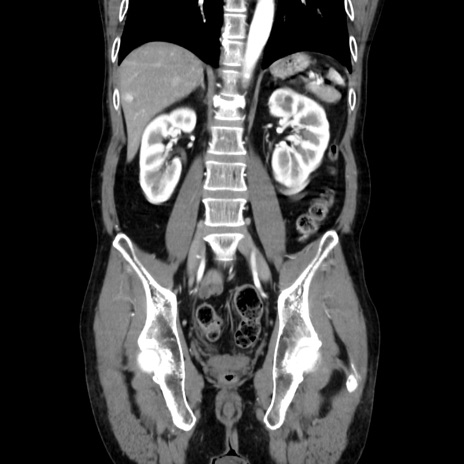

症例37(冠状断像)

【症例】40歳代 男性

【主訴】腹痛

【現病歴】4時間ほど前に電車に乗車中に臍部上より腹痛出現。徐々に増悪し起立困難となり、救急外来受診。生ものは数日食べていない。今朝お雑煮を食べた。

【身体所見】BT 36.8℃、BP 117/84mmHg、HR 91/min、SpO2 97%、苦悶様、腹部:臍上部広範囲圧痛あり、反跳痛±

【データ】WBC 8100、CRP 0.03